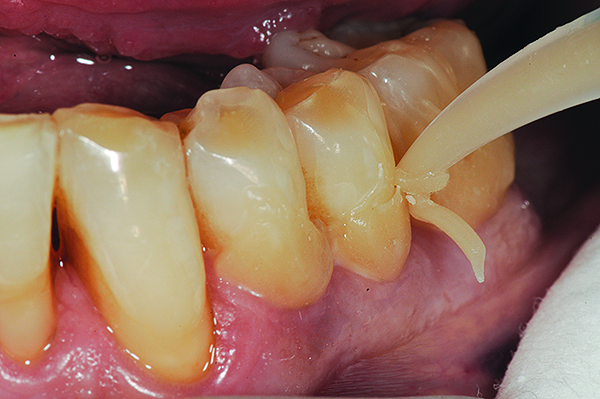

Fig 6. In Case 2, pretreatment view of multiple non-carious cervical lesions.

Figure 6